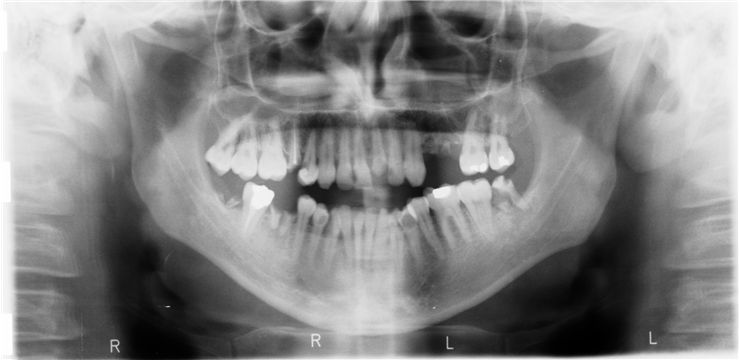

Picture Of Mouth Radiography Broken Tooth